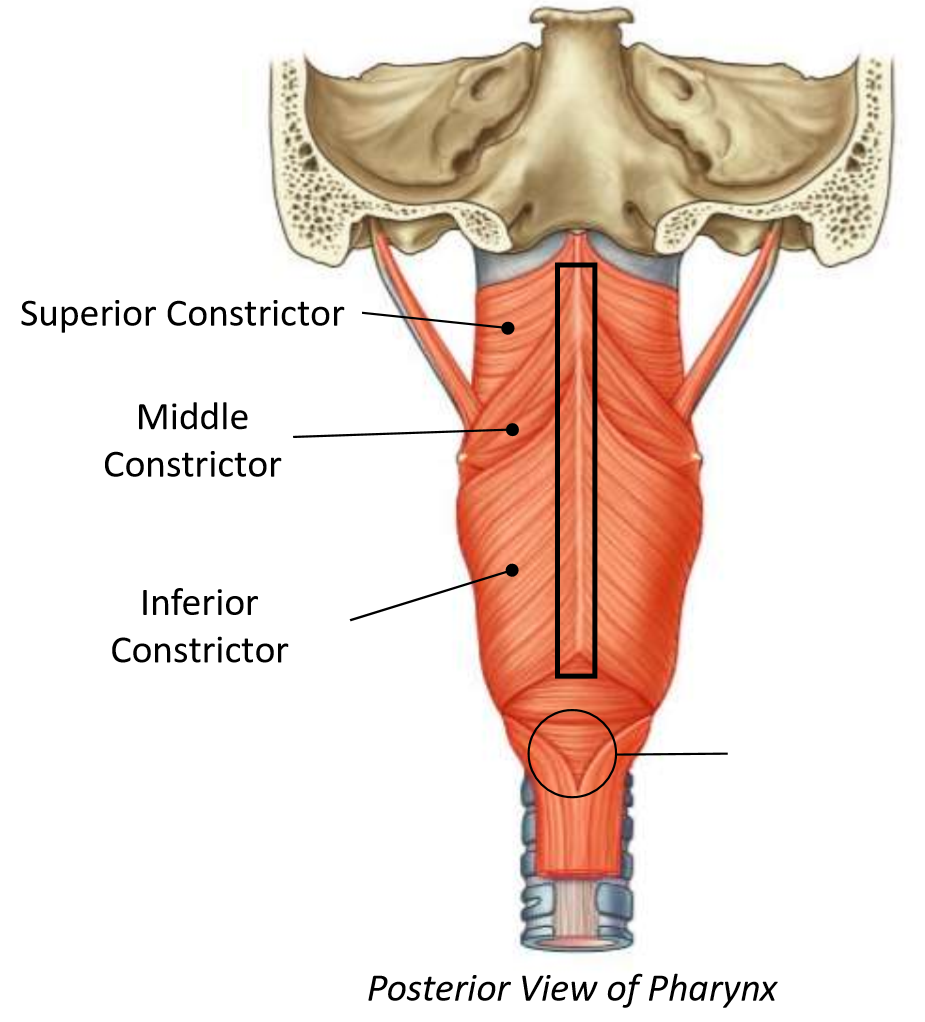

What muscle is this?

superior constrictor

What is the upper border of this muscle?

palatopharyngeal sphincter

What is 1?

pterygomandibular raphe

What is 2?

stylohyoid ligament

What are the attachments of this muscle?

pterygoid hamulus, pterygomandibular raphe, posterior end of mylohyoid line → pharyngeal raphe

What is this muscle?

middle constrictor

What are the attachments of this muscle?

lower stylohyoid ligament, lesser and greater horns of hyoid → pharyngeal raphe

What muscle is this?

inferior constrictor

Which part of the muscle is 1?

thyropharyngeus

Which part of the muscle is 2?

cricopharyngeus

What are the attachments of this muscle?

oblique line of thyroid cartilage, cricothyroid tendon, cricoid cartilage → pharyngeal raphe

What is in the rectangle?

pharyngeal raphe

What is in the circle?

killians dehiscence